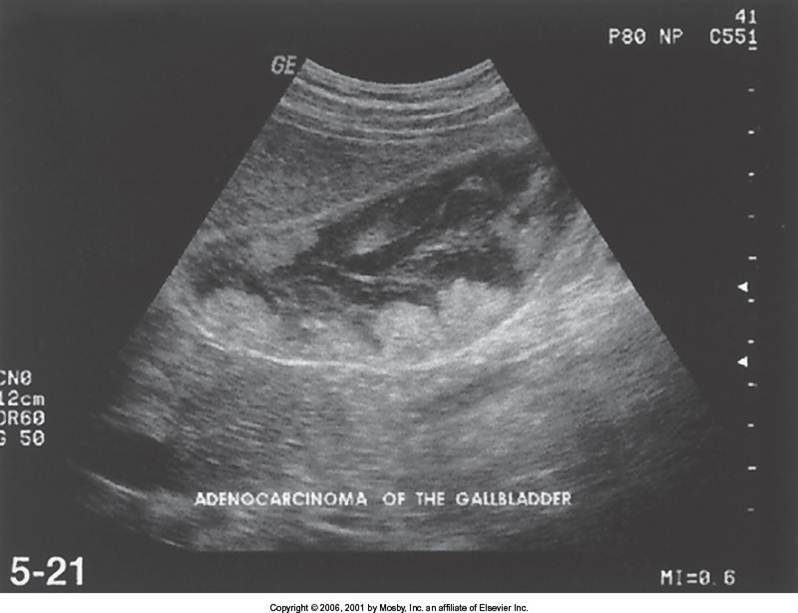

Gallbladder Carcinoma